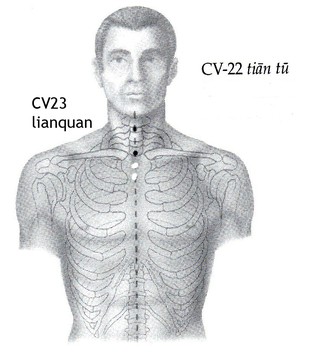

CV-22 tiantu, finestra del Cielo

CV-23 lianquan, Corner Spring

Tiantu è un punto importante in alcuni esercizi di Qigong, in particolare per stimolare il Qi del sistema Polmoni; utilizzato in caso di tosse, asma e problemi alla gola quale Flegma e catarro. E' utile anche per chi soffre per problemi alla voce soprattutto nei casi di Deficit di Yin. Si trova al centro della fossa sovrasternale.

Lianquan, subito sopra CV-22, riguarda la perdita di voce o l'eloqio difficile nei casi di Deficit di Yin.